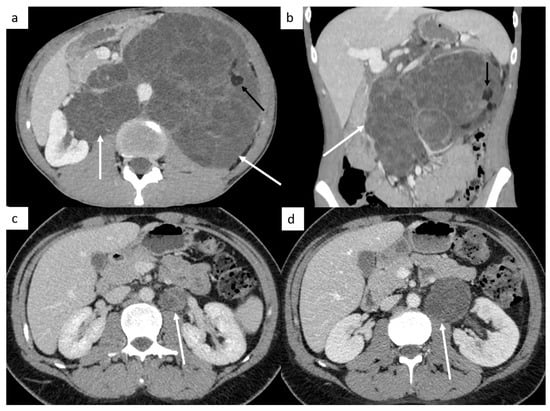

Other sites include liver, bones and rarely, testicular metastasis may occur to adrenals, kidneys, spleen, pleura, pericardium, peritoneum or retroperitoneum in very advanced disease (Figure 2). In case of large retroperitoneal lymph nodes, an extension may occur into the inferior vena cava in the form of tumor thrombus (Figure 2).

Figure 2.

Other sites of metastatic disease. In advanced stages, abdominal CT can show different sites of metastases including liver ((a,b), black arrows), peritoneal carcinomatosis ((b), white arrows), retroperitoneal carcinomatosis (c), cutaneous metastases in front of pubis (d). In case of large retroperitoneal lymph nodes ((e), white arrows), a tumor thrombus in the inferior vena cava can be found ((e), black arrows). Spinal bone CT shows several vertebral metastases (f).